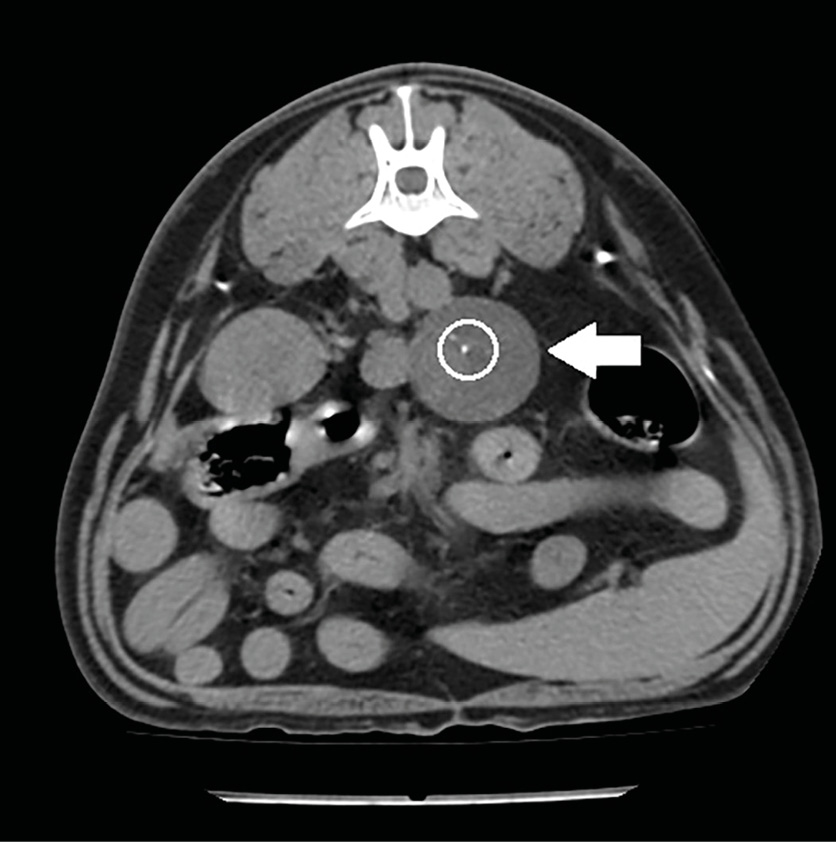

La tomografía computarizada (TC) es una técnica que va a emplearse habitualmente de forma previa a la cirugía en masas adrenales caninas, debido a que se considera más precisa que la ecografía para la detección de invasión vascular: tiene una sensibilidad y especificidad aproximada del 90 %28,29 (imagen 5) y esto es de gran importancia ya que, si existe invasión vascular, el abordaje quirúrgico será diferente.

Imagen 5. Imágenes de TC en ventana de tejidos blandos en fase venosa tras la administración de contraste reconstruidas en planos sagital (A) y dorsal (B) donde se observa un defecto de llenado de la vena cava caudal (círculo negro) por la presencia de una masa hipoatenuante de 4 cm de longitud que se corresponde con un tromoboembolismo tumoral a través de la vena frénico abdominal (*) por un feocromocitoma en la glándula adrenal izquierda (M).

Además, la presencia, el tamaño y la extensión del trombo van a tener un impacto sobre el pronóstico29. Recientemente se ha descrito un sistema de clasificación que puede ser de ayuda para determinar si existe o no invasión vascular, ya que en ocasiones puede resultar complicado porque, debido al gran tamaño de las masas, puede producirse una compresión vascular que dificulta la exploración29.